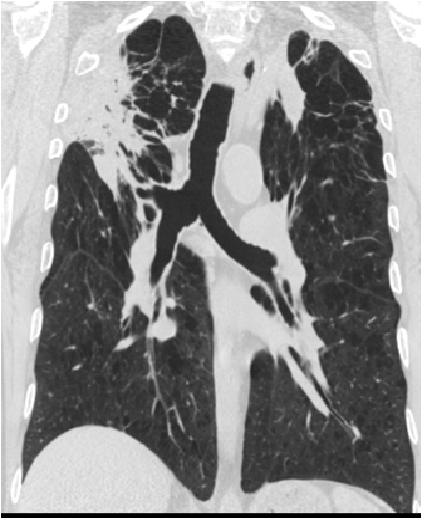

השימוש בדבק ביולוגי (Aeris Therapeutics, Mass, USA) נועד לפעול ברמת בועיות הריאה ודרכי האוויר הקטנות. החדרה של חומר קצפי שבסיסו גלוטראלדהיד (Glutaraldehyde) לבועיות הריאה גורם ליצירה של דלקת ריאות כימית מבוקרת כאשר בתהליך הריפוי של אותה דלקת נוצרת רקמה צלקתית הגורמת למשיכה ולהקטנה של רקמת הריאה וצמצום של נפחה (תמונה מס' 1). החומר, הידרוגל (Hydrogel), מוחדר באמצעות ברונכוסקופ גמיש דרך קטטר מיוחד תחת אלחוש קל בכמות של 10 מיליליטר (מ"ל) לכל תת יחידה (Sub-segment) של הריאה[10],[11],[12],[13].

במרכז הרפואי רבין עוסקים בטיפול בנפחת באמצעות שיטה זו מאז שנת 2009. עד שנת 2015 עברו את הפעולה במחלקה כ-45 חולים הלוקים בנפחת גם הטרוגננית וגם הומוגנית. אוכלוסיית החולים כללה חולים במחלת ריאות חסימתית קשה עם FEV1 ממוצע של 34% מהצפוי. משך הפעולה נע בין 5 ל-10 דקות כאשר החולים עוברים את הפעולה במסגרת אשפוז יום ולאחר 6 שעות השגחה משוחררים לביתם. במהלך הפעולה מטפלים בארבעה תתי יחידות שאותם בוחרים לפי בדיקת טומוגרפיה ממוחשבת (CT, Computed Tomography) ומיפוי ריאות, כאשר הטיפול נעשה דו צדדית באותה פעולה.

תופעות הלוואי העיקריות שבהן נתקלו במחלקה הן החמרה של מחלת הריאות החסימתית בכ-20% מהחולים, דלקת ריאות ב-2 חולים ומחלת חום המלווה בשקיעת דם מוחשת ועלייה בספירת הכדוריות הלבנות בכ-50% מהחולים הנובעת מתגובה סיסטמית לחומר המוזלף. תגובה זו נמשכת כ-1-2 ימים וניתנת להקלה משמעותית על ידי שימוש מניעתי בסטרואידים ונוגדי דלקת לא סטרואידליים (NSAID, Nonsteroidal anti-inflammatory drugs). לאחר ניסיון מצטבר של קרוב לשנה וחצי בסיכום ביניים נצפה שיפור סובייקטיבי אצל קרוב ל-67% מהחולים. שיפור של 12% ב-FEV1 הושג ב-27% מהחולים, והירידה הממוצעת בכליאת האוויר היתה 11.7. שיפור זה התבטא קלינית בעלייה ממוצעת של 28% במרחק הליכה ל-6 דקות ובשיפור של 13 נקודות במדד קוצר הנשימה.